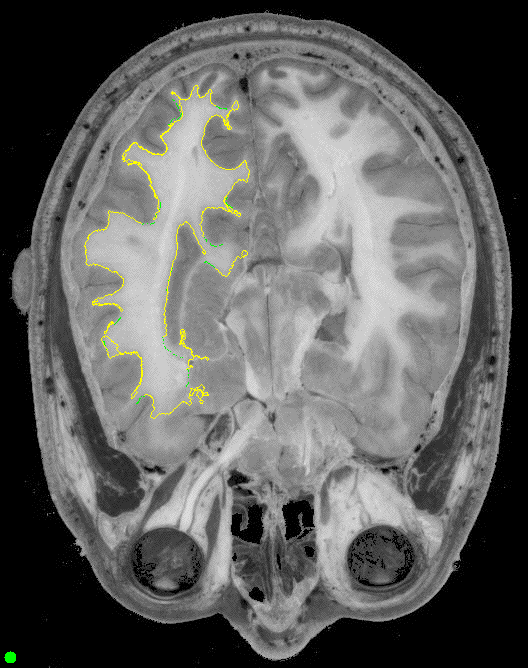

Here's what we get when we try to trace the ventricles.

We did this on two slices at roughly the same locations from different

subjects. We first traced by hand the

green pixels at the edge of the larger ventrical to the left in an image.

Then we used the resulting neural net to trace the other regions.